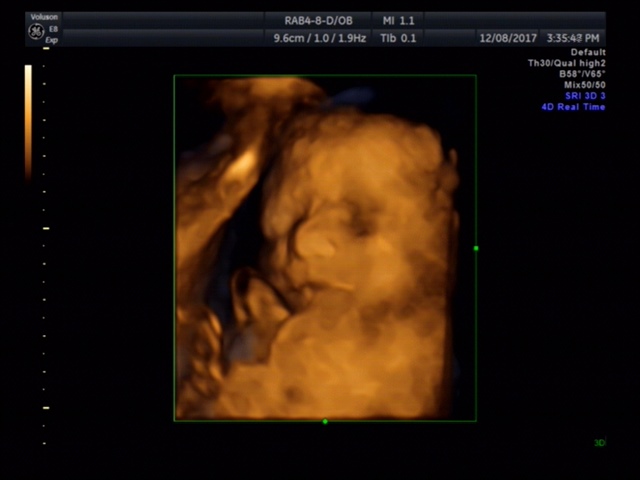

JESSICA👣

宝宝3个月12天

孕12周+4天

鼻子应该很高,好看^_^

JESSICA👣[帖主]:医生说鼻子很像我是个高鼻梁水滴鼻,嘴唇的轮廓也有点像,其他就不清楚了。